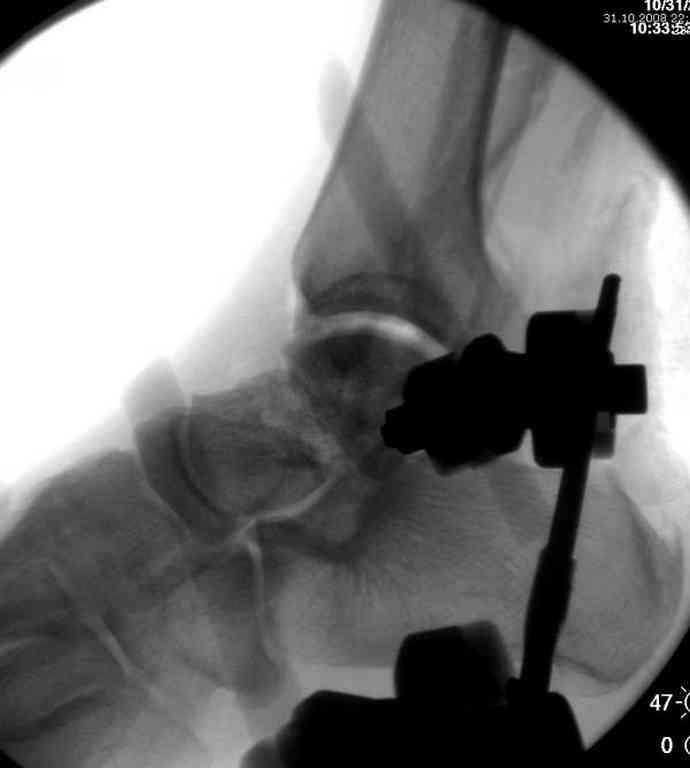

10 дней назад поступил с открытым повреждением медиальной лодыжки и переломо вывихом таранной кости. Ургентно сделана репозиция с наложением наружного фиксатора + Irrigation&Debridment.

Во время репозиции выявили повреждение заднего сухожилия м. тибиалис и задней большеберцовой артерии. Медиальную рану удалось закрыть частично и установлен вакуум.

Дважды провели Irrigation&Debridment с заменой вакуума.

Вчера провели фиксацию.